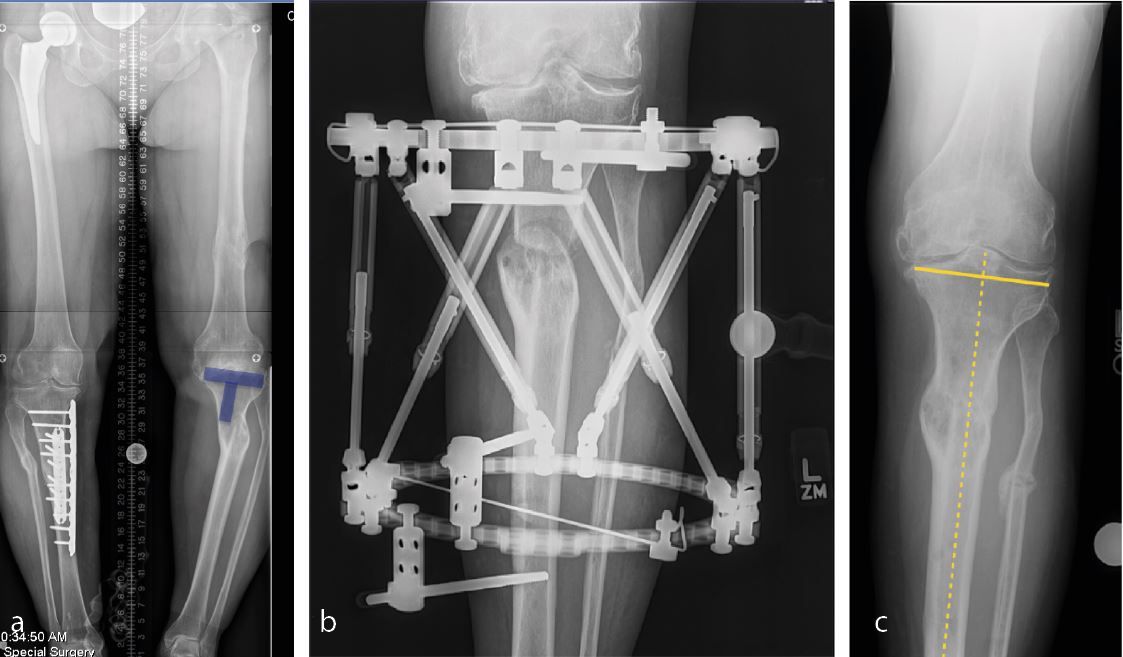

The clinical articles address two major domains. In revision acetabular surgery, contributions examine cup-cage reconstruction for severe acetabular bone loss and pelvic discontinuity alongside patient-matched 3D-printed implants for Paprosky 3 acetabular defects guided by bone quality assessment. In primary knee arthroplasty, the issue explores an extension gap first technique applying adjusted mechanical alignment to minimize soft tissue releases, complemented by a systematic approach to total knee arthroplasty in posttraumatic osteoarthritis.